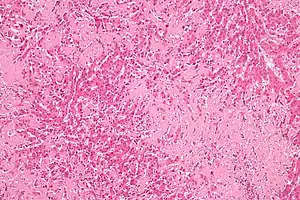

| Micrograph of liver amyloidosis, H&E stain |